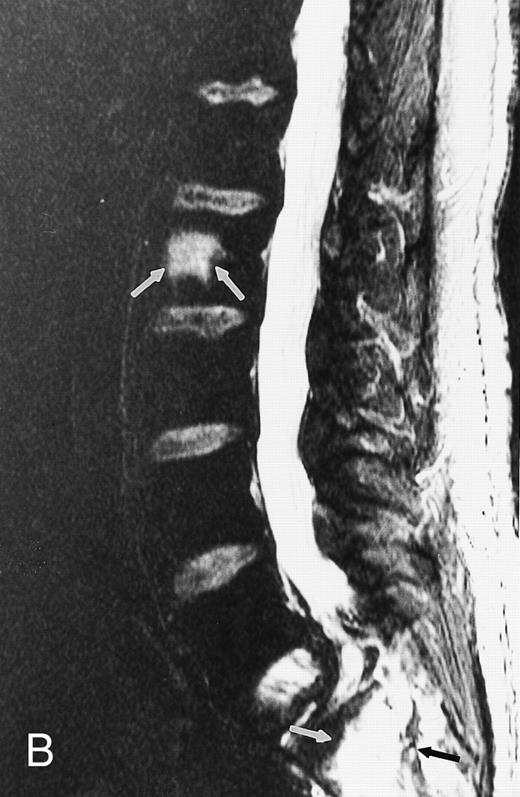

Diffuse MR pattern of abnormal marrow in a 29-year-old man with AML: T1-weighted sagittal (500/10, TR/TE) (A), T2-weighted, fat-suppressed fast spin echo sagittal (5000/96, TR/TE, ET 16) (B), and enhanced T1-weighted sagittal (500/10, TR/TE) (C) MR images of the thoracic spine. The abnormal vertebral bodies in (A) are dark and isointense to the intervertebral discs and in (B) they become bright. In (C), the abnormal marrow enhances and the vertebrae become brighter than the discs. Note extraosseous mass (arrowheads) in the posterior epidural space with preservation of the bony cortex.